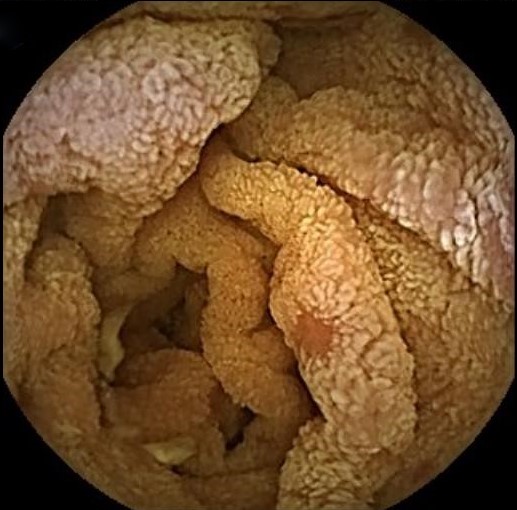

A challenging case of chronic diarrhea

Isabel Garrido, Armando Peixoto, Hélder Cardoso, Guilherme Macedo

Serviço de Gastrenterologia, Centro Hospitalar Universitário de São João

A 74-year-old Caucasian woman, without relevant past medical history, was admitted due to weight loss, abdominal pain and diarrhea for a year. Blood tests showed severe hydroelectrolytic and nutritional disorders. Upper endoscopy and colonoscopy had no relevant changes. Capsule endoscopy revealed extensively scattered lymphangiectasias, areas with shortened villi and some erosions in the jejunum and ileum. The histological examination showed severe mucosal atrophy, crypt hyperplasia and lymphoplasmacytic infiltration in the lamina propria, without significant intraepithelial lymphocytosis. Towards the diagnosis of autoimmune enteropathy, treatment with corticosteroids was started, with a quick improvement of symptoms and nutritional deficits.